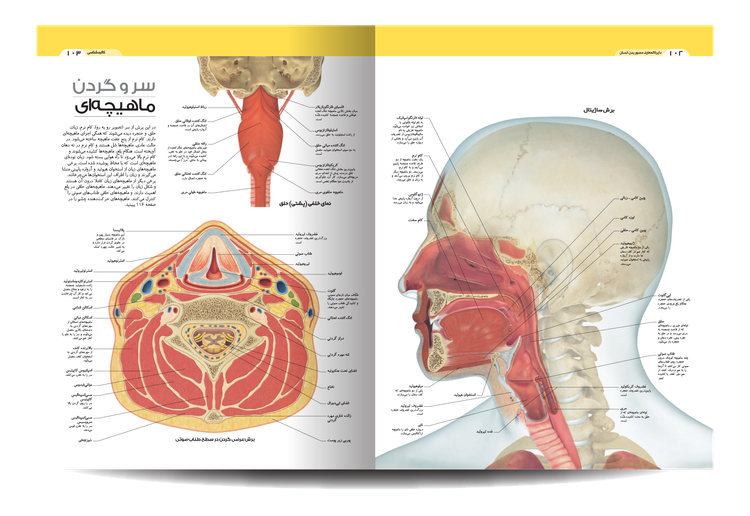

کتاب «دایره المعارف مصور بدن انسان» ، نگاهی دقیق به فرمها و عملکردهای بدن در فیزیولوژی و آناتومی ارائه میدهند و نحوه عملکرد بدن و سیستمها و تواناییهای شگفتانگیز آن را نشان میدهند.

آناتومی زیبای ما را ببینید و نحوه عملکرد اسکلت، ماهیچه ها و رباط ها را بخوانید. این ویرایش دوم شامل جزئیات بیشتری در مورد مفاصل دست و پا است. کتاب «دایره المعارف مصور بدن انسان» شما را از دوران نوزادی تا پیری می برد و نشان می دهد که بدن ما چگونه رشد می کند و تغییر می کند و چه چیزی ممکن است اشتباه باشد.

این راهنمای تصویری از تصاویر و نمودارهای قابل توجهی برای نگاه کردن به بدن پیچیده و شگفتانگیز ما استفاده میکند. این در قالبی ساده و با توضیحات ساده نوشته شده است تا بهترین نمای کلی از بسیاری از چیزهایی را که ما را انسان میسازند به شما ارائه دهد.